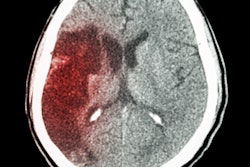

"We used a single-stage, end-to-end, fully convolutional neural network to achieve accuracy levels comparable to that of highly trained radiologists, including both identification and localization of abnormalities that are missed by radiologists," wrote study authors Dr. Esther Yuh, PhD, of UCSF; Jitendra Malik, PhD, of UC Berkeley; and colleagues.

"Algorithm performance exceeded that of 2 of 4 American Board of Radiology (ABR)-certified radiologists with attending-level experience ranging from 4 to 16 [years]," the authors wrote. "In addition, PatchFCN achieved 100% sensitivity at specificity levels approaching 90%, making this a suitable screening tool for radiologists based on an acceptably low proportion of false positives."

The researchers said they are now applying the algorithm in a research study led by Dr. Geoffrey Manley, PhD, a professor and vice chair of neurosurgery at UCSF. That study will include CT scans from trauma centers across the U.S.